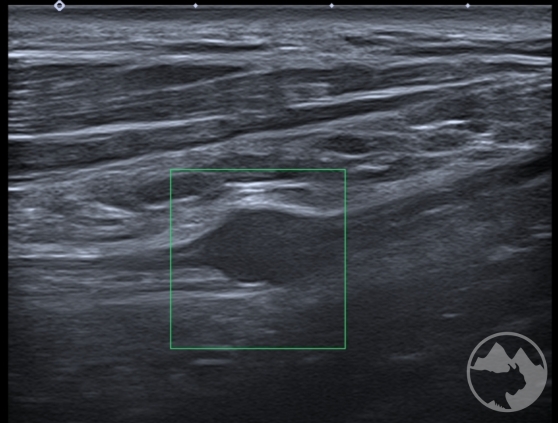

Workshop bude zaměřen nejen na samotné zobrazení daných nervů ve svém průběhu, nýbrž i na důležité topografické souvislosti s dalšími strukturami jako jsou kosti, svaly, cévy, vazy nebo fascie a na identifikaci anatomických „markerů“ a rizikových míst. V rámci několika přednášek budou zopakovány anatomické průběhy nejčastěji vyšetřovaných nervů včetně běžných variací, budou prezentovány možnosti měření, správného nastavení dopplerovského módu, ukázky úžinových syndromů a jiných patologických nálezů včetně důležitých „redflags“. Převažovat však budou praktické ukázky vyšetření a nácviky v malých skupinách. Vyšetřovací postupy zahrnou běžné statické zobrazení i skenování při pohybu, tzn. testy neurodynamiky. K dispozici na vyzkoušení budou standardní sondy i moderní vysokofrekvenční sondy s rozlišením umožňujícím hodnocení jednotlivých nervových fasciklů. Součástí přednášek ani praktických nácviků nebudou intervenční postupy.